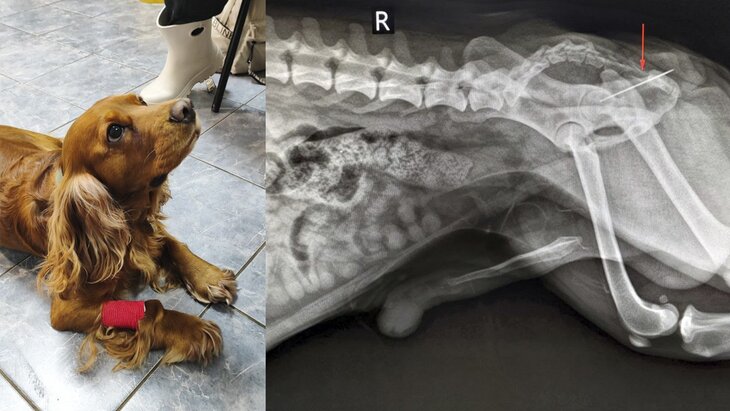

Специалисты ветклиники Коптево помогли кокер-спаниелю по кличке Вольт, проглотившему швейную иглу. Об этом Москве 24 рассказали в столичной госветслужбе.

"При осмотре терапевт Анна Кубатина заметила, что из заднего прохода Вольта торчит швейная нитка. Пациента срочно отправили на рентген", – рассказали в пресс-службе.

Снимок показал, что за ниткой тянулась и игла, которая застряла в прямой кишке. Ветврачи отметили, что случай уникальный: проглоченная игла беспрепятственно миновала весь жедудочно-кишечный тракт собаки и застряла уже в конце.

Далее Вольт попал к хирургу Евгению Бахтину и анестезиологу Светлане Дорожкиной, которые благополучно извлекли иглу, после чего Вольта отправили домой.